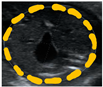

Biometrical data measured at euthanasia are shown in Table 2. By comparison (Wilcoxon matched-pairs signed rank test) to values obtained with ultrasound measurements at G35, no significant differences were identified, with an estimated ultrasound accuracy of 1.17%. Using histological analyses, three macrostructures of the placenta could be identified at G35: the decidua, subplacenta, and labyrinth + interlobium (Figure 4A). However, at G60 the subplacenta was absent (Figure 4B). Ultrasound screening was unable to differentiate placental structures at any gestational age studied.

Figure 4.

Placental structure at G35 and G60. Placental structure at (A) gestational day 35 and (B) gestational day 60. Green line = decidua. Dark-blue line = subplacenta. Orange line = interlobium and labyrinth zone. Scale = 5 mm.